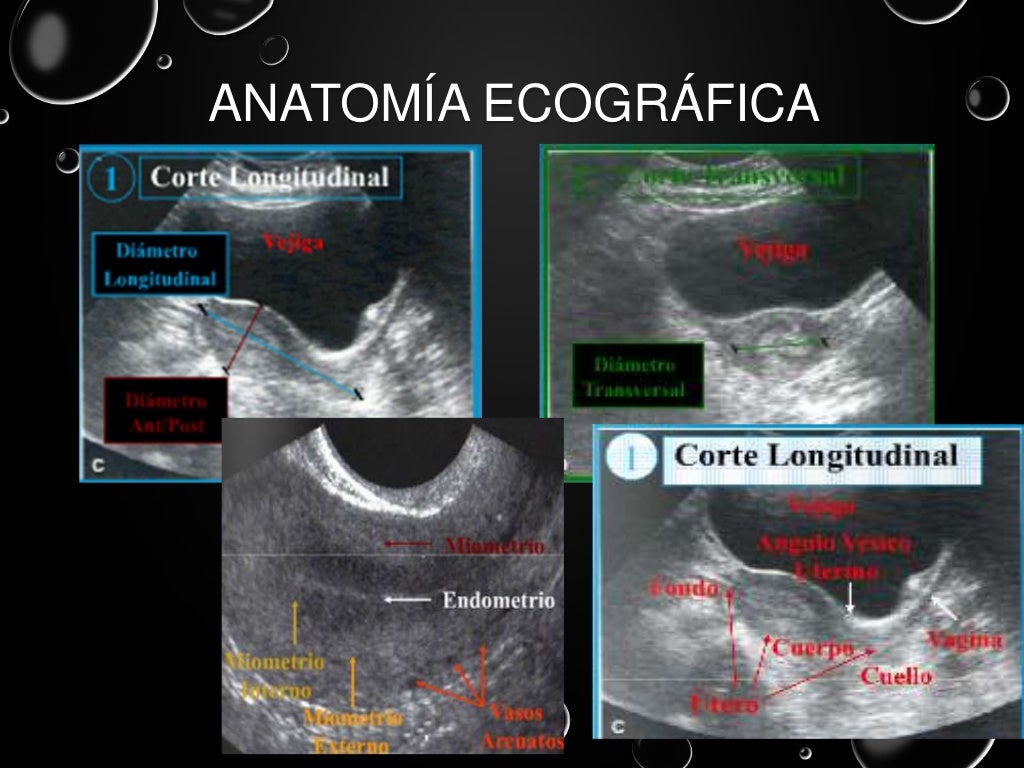

ultrasonido pelvico salud digna El precio del ultrasonido pélvico en salud digna laboratorios puede variar ya que hay varios tipos de ultrasonido que componen la zona pélvica. Ultrasonido de abdomen con un costo de $105. Las imágenes ecográficas del ultrasonido pélvico pueden también ayudar a determinar posibles quistes ováricos o fibromas uterinos, así como cáncer ovárico o uterino. Un ultrasonido o ecografía es un procedimiento seguro que utiliza ondas de sonido no audibles para el ser humano, las cuales escanean diferentes partes del cuerpo, con el propósito de crear una imagen del interior. El ultrasonido pélvico es primordial para diagnosticar el origen del dolor pélvico, sangrado anormal, u otros problemas menstruales. En un ultrasonido obstétrico, se explora tu abdomen y cavidad pélvica durante el embarazo, con lo que es posible. Un ultrasonido intravaginal también puede ayudar a diagnosticar problemas de fertilidad en la vejiga, los riñones y la cavidad pélvica. Ultrasonido 4d con un costo de $230.

Ultrasonido pelvico

Ultrasonido pelvico